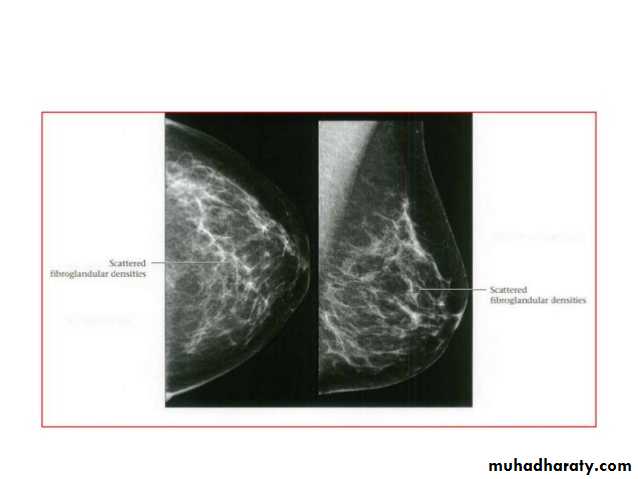

Breast density & who can U detect a mass lesion

Your mammogram report must take in consideration & assessment the breast density. Breast density is based on how fibrous and glandular tissue tissues are distributed in your breast, vs. how much of your breast is made up fatty tissue.

Dense breasts are not abnormal, but they are linked to a higher risk of breast cancer. We know that dense breast tissue can make it harder to find cancers on a mammogram. Still experts do not agree what other tests, if any, should be done in addition to mammograms in women with dense breasts who aren’t in a high-risk group (based on gene mutations, breast cancer in the family, or other factors